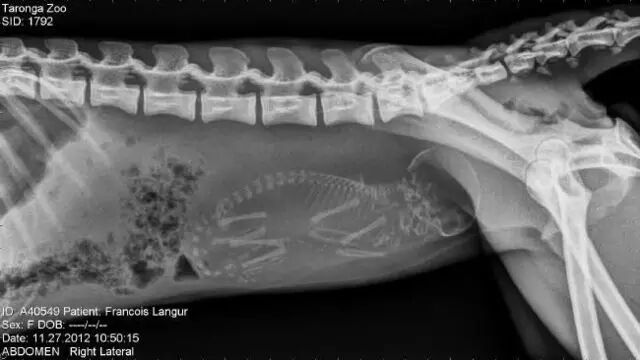

怀孕是一件神圣而又带有神秘色彩的事,她预示着新生命的来临。在动物世界,怀孕是怎样的一种奇迹,以下 14 种动物在怀孕期间的 X 线图片,我们可以通过全新的影像视角探查一番。

• 猴子